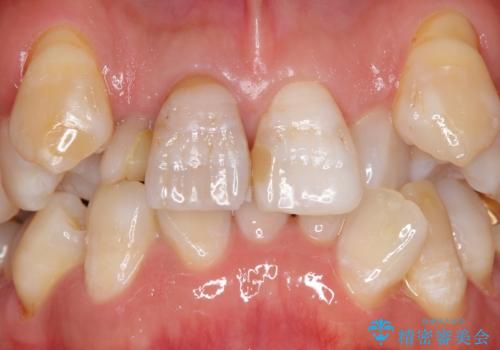

重度の叢生(歯並びのがたがた)のため、

①小臼歯抜歯でしっかりと歯並びを整える矯正治療

②前歯のセラミック治療を行いやすくするための補綴前矯正

の2つの治療方針を提案しました。

患者様の「できるだけ短期間で治療を終わらせたい、セラミックが入れられたら良いので大がかりなことはしたくない」とのご要望により、3Dシミュレーションを何度も行い患者様とのコンサルを重ね、上顎左右犬歯と左下2を抜歯して②のプランである補綴前矯正(インビザライン)を行うことにしました。

寿命が長く機能的に重要な役目を果たす犬歯を抜くリスクや、矯正治療の仕上がりに限界があることをご理解頂いた上で治療を行っております。